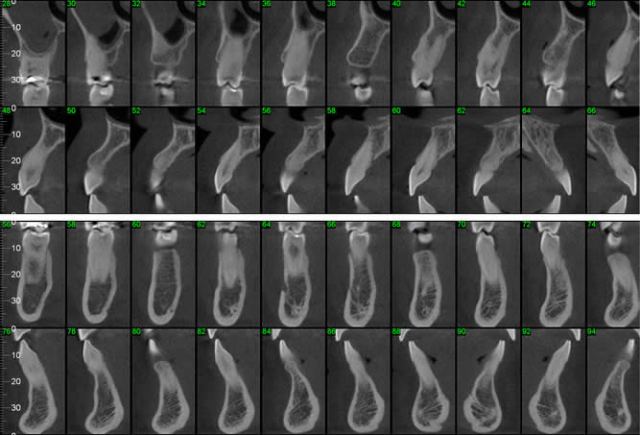

CASO 2 - Localização de dente retido

História clínica de exodontia do dente 38 há um ano, sem no entanto localizar o elemento dentário acreditando que o paciente havia engolido o dente. Na radiografia panorâmica observa-se a presença do dente 38 superposto ao ramo. Na tomografia localiza-se o dente no assoalho bucal.

CASO 5 - Dente Retido

Dente 47 e 48 retidos, em posição mésio horizontal, sobrepostos com raízes superpostas ao canal mandibular. Ao exame tomográfico identifica-se o canal passando rechaçado entre os ápices do 48 e a cortical vestibular e passando entre as duas raízes mesiais do dente 47.